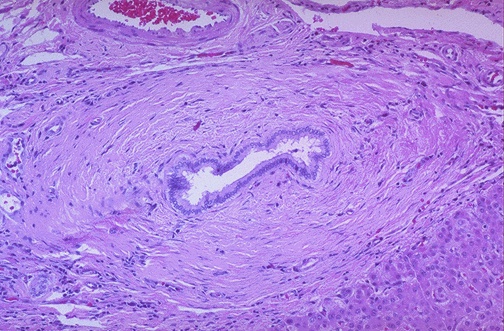

| Microscopically, this bile duct in a case of primary sclerosing cholangitis (PSC) is surrounded by marked collagenous connective tissue deposition with atrophy of the epithelium and narrowing of the lumen. The alkaline phosphatase is markedly elevated. Patients can have icterus and pruritis. Males from 20 to 50 years of age are most often affected. |